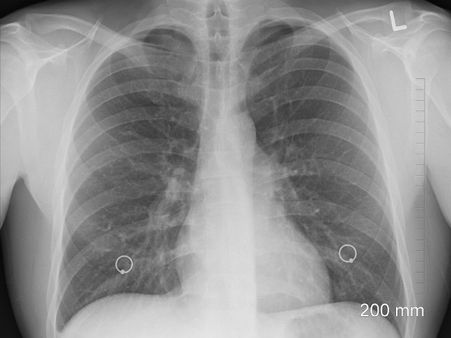

একাধিক গবেষণায় দেখা গেছে কলকাতার মতো বায়ু দূষণের ঘেরাটোপে থাকা শহরে যদি কেউ কুয়াশার মধ্যে অনেকটা সময় কাটান, তাহলে শরীরের মারাত্মক ক্ষতি হয়। বিশেষত ফুসফুসের। শুধু তাই নয়, ধীরে ধীরে একাধিক মারণ রোগও ঘারে চেপে বসে। প্রসঙ্গত, বড়দের থেকেও বাচ্চাদের শরীরের উপর কুয়াশের প্রভাব বেজায় ভয়ঙ্কর হয়। তাই তো এমন সময় বাচ্চাদের অতিরিক্ত সাবধানে রাখতে হবে।

কয়েক মাস আগে প্রকাশিত এক রিপোর্টে এমনটা দাবি করা হয়েছিল যে বায়ু দূষণের দিক থেকে আমাদের শহর কলকাতা দেশের বাকি সব মেট্রোপলিটন শহরকে পিছনে ফেলে দিয়েছে। এমন পরিস্থিতি কুয়াশার মাত্রা বাড়ার আশঙ্কা রয়েছে। আর এমন দূষিত কুয়াশার মধ্যে সময় কাটালে স্বাভাবিকভাবেই ফুসফুসের অন্দরে দূষিত বায়ু ভরে যায়। ফলে অ্যাস্থেমার মতো রোগে আক্রান্ত হওয়া আশঙ্কা বাড়ে।

২. ক্রণিক ব্রঙ্কাইটিস:

কুয়াশার প্রভাবে সাধারণত যে যে রোগগুলি বেশি মাত্রায় মাথা চাড়া দিয়ে ওঠে, সেগুলির মধ্যে অন্যতম হল ব্রঙ্কাইটিস। এক্ষেত্রেও ডাস্ট পার্টিকাল এবং দূষিত বায়ু ফুসফসুকে কমজোরি করে দিয়ে এমনসব রোগের পথকে প্রশস্থ করে। সেই কারণেই তো বাচ্চা এবং বয়স্কদের কুয়াশার মধ্যে বেরতে মানা করেন চিকিৎসকেরা।

৩. লাং প্রবলেম:

একাধিক গবেষণায় একথা প্রমাণিত হয়ে গেছে যে কুয়াশার কারণে সারা দেহের মধ্যে সবথেকে বেশি ক্ষতিগ্রস্থ হয় ফুসফুসই। ফলে শ্বাস কষ্টের মতো সমস্যা মাথা চাড়া দিয়ে ওঠার সম্ভাবনা থাকে। সেই কারণেই তো শীতকালে খুব সকালে কুয়াশার মধ্যে মনিং ওয়াক করতে মানা করা হয়ে থাকে।

কুয়াশার মধ্যে সবথেকে বেশি পরিমাণে থাকে এই গ্যাসটি, যা শরীরে প্রবেশ করার পর ফুসফুসের টিস্যুদের দুর্বল করে দিতে থাকে। সেই সঙ্গে ফুসফুসের কর্মক্ষমতা মারাত্মক কমিয়ে দেয়। ফলে নানাবিধ ক্রমিক রেসপিরেটরি প্রবলেমে আক্রান্ত হওয়ার আশঙ্কা বৃদ্ধি পায়।